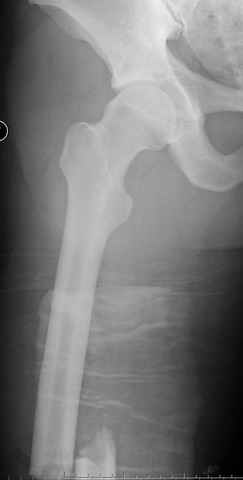

перелом бедра

постоперационные

|